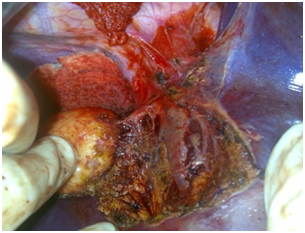

Figure 3 Multiple hydatid cysts in the right lobe of the liver in 9 years old girl. Multiple total pericystectomy with closed cysts was performed.

Sixteen cysts were excised in 10 patients. Nine patients underwent radical surgery; 5 had multiple cysts and were submitted to hepatic resection (1 right and 2 left hepatectomy) or multiple total pericystectomy with closed cyst. Four patients with single cyst underwent total pericystectomy with closed cyst. Only 1 patient underwent a non-radical operation and a subtotal pericystectomy was performed. In this case the cyst was opened and a small piece of the pericystium was left in place close to the right branch of the portal vein and the bile duct. A cysto-biliary fistula with the right posterior bile duct was sutured after washing of the biliary tree. Only in one case intermittent Pringle maneuver was used to control bleeding. In the other cases the inflow was controlled by selective clamping, if necessary. In 2 cases previous clamping at the origin of the right hepatic vein was performed before dissection of the vein from the pericystium. Intraoperative ultrasound was necessary only in one case of subtotal pericystectomy. It was always possible to dissect the main veins from the pericystic wall (Figure 2-4), while it was necessary to sacrifice the structures of the portal triad when they were fused in the pericyst. Mean operative time was 236 min. All patients were extubated at the end of the procedure. Mean postoperative stay was 5.2± 2,52 days (range 3-10), with no mortality and only 1 low output biliary fistula in the case of subtotal pericystectomy that healed after 9 days. Postoperative stay was longer for children because they lived far from the hospital. Mean follow up is higher than 3 years and until now no recurrence were observed (Figure 5).